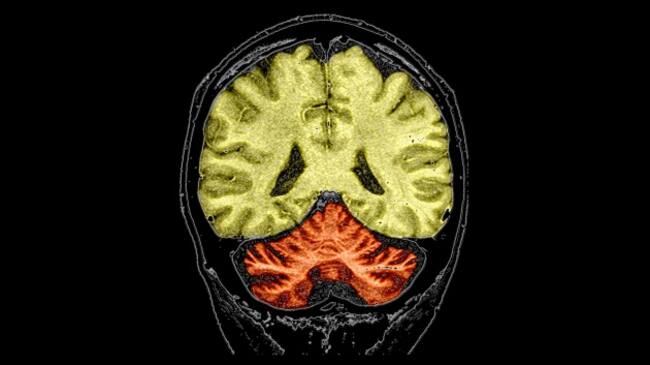

Resonancia magnética coloreada de un paciente con un largo historial de abuso de alcohol